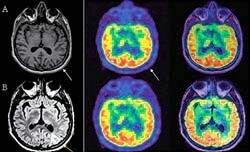

• Imágenes diagnósticas

Imágenes diagnósticas

La tomografía por emisión de positrones (PET) y la resonancia

magnética de contraste (FMRI), que permiten la visualización de la actividad cerebral en tiempo real, es decir, en el momento de leer, hablar, dibujar, memorizar, pensar, etc